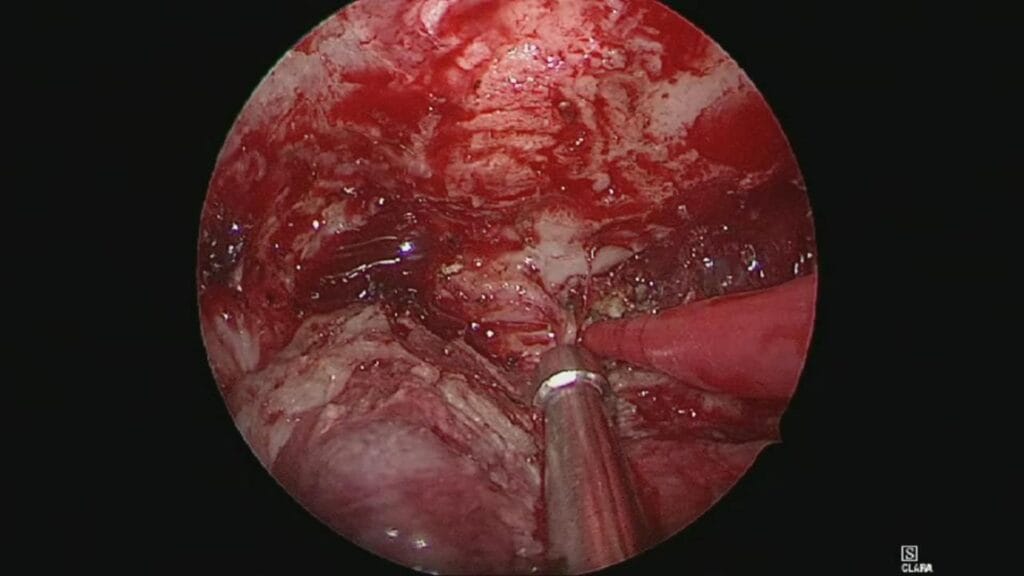

Resección de neurinoma del acústico por abordaje translaberíntico

El Dr. Rubén Polo realiza resección microquirúrgica de neurinoma del acústico por abordaje translaberíntico.